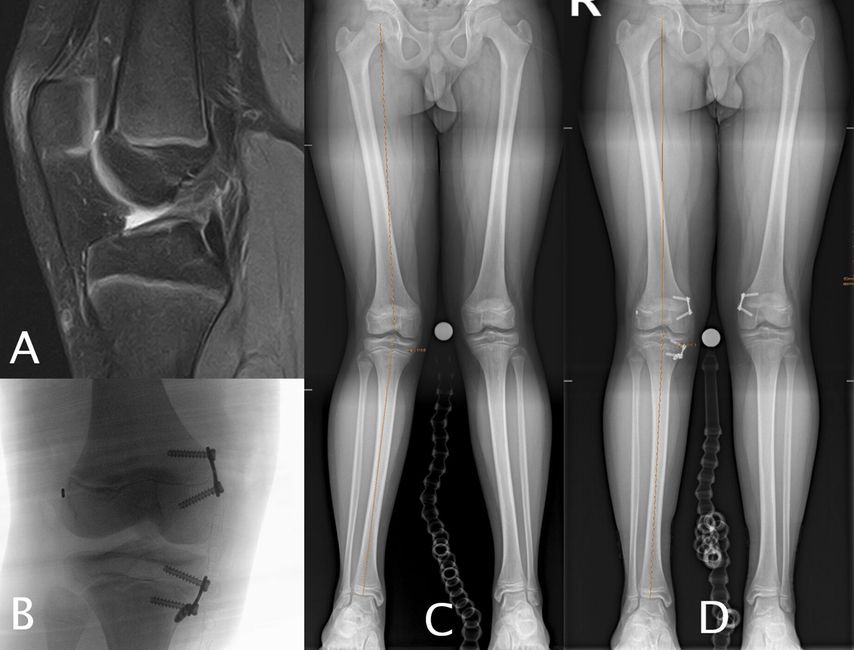

Entsprechend konnte gezeigt werden, dass die kombinierte Korrektur von Varus und tibialem Slope unter axialer Belastung zu einer deutlichen Reduktion der VKB-Transplantatkräfte – in experimentellen Modellen um bis zu 58% – führt.35 In Revisionssituationen mit varischer Beinachse und gleichzeitig steilem tibialem Slope stellt daher eine biplanare Osteotomie mit kombinierter Varus- und Slope-Korrektur, ergänzt durch eine simultane oder zweizeitige VKB-Rekonstruktion, die biomechanisch sinnvollste Strategie dar.23,50 Der Einsatz patientenspezifischer Instrumente (PSI) kann dabei die Präzision der kombinierten Varus- und Slope-Korrektur erhöhen und ist eine sinnvolle Unterstützung der präoperativen Planung sowie der intraoperativen Umsetzung (Abb. 3).

Abb. 3: 33-jährige weibliche Patientin mit zweifacher VKB-Reruptur (A) mit einem erhöhten tibialen Slope von 15° (B) und einer Valgusfehlstellung von 3° (C), behandelt mit einer einzeitigen Revision mitipsilateralem Quadricepssehnengraft und einer varisierenden Slope-reduzierenden HTO (D, E, F)